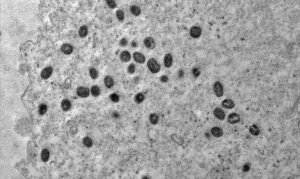

China estabelece controle para pessoas e bens vindos de países atingidos pela Mpox Medidas de vigilância e precaução em vigor…

A OMS declara emergência em saúde pública global devido à mpox na África A Organização Mundial da Saúde (OMS) declarou…

O surgimento da mpox como emergência em saúde pública internacional Após recomendação de especialistas e autoridades sanitárias internacionais, o alerta…

Avaliação de surto de Mpox na África preocupa a OMS A Organização Mundial da Saúde (OMS) convocou um comitê de…

Emergência de saúde pública na África por mpox O Centro de Controle e Prevenção de Doenças (CDC África) declarou o…